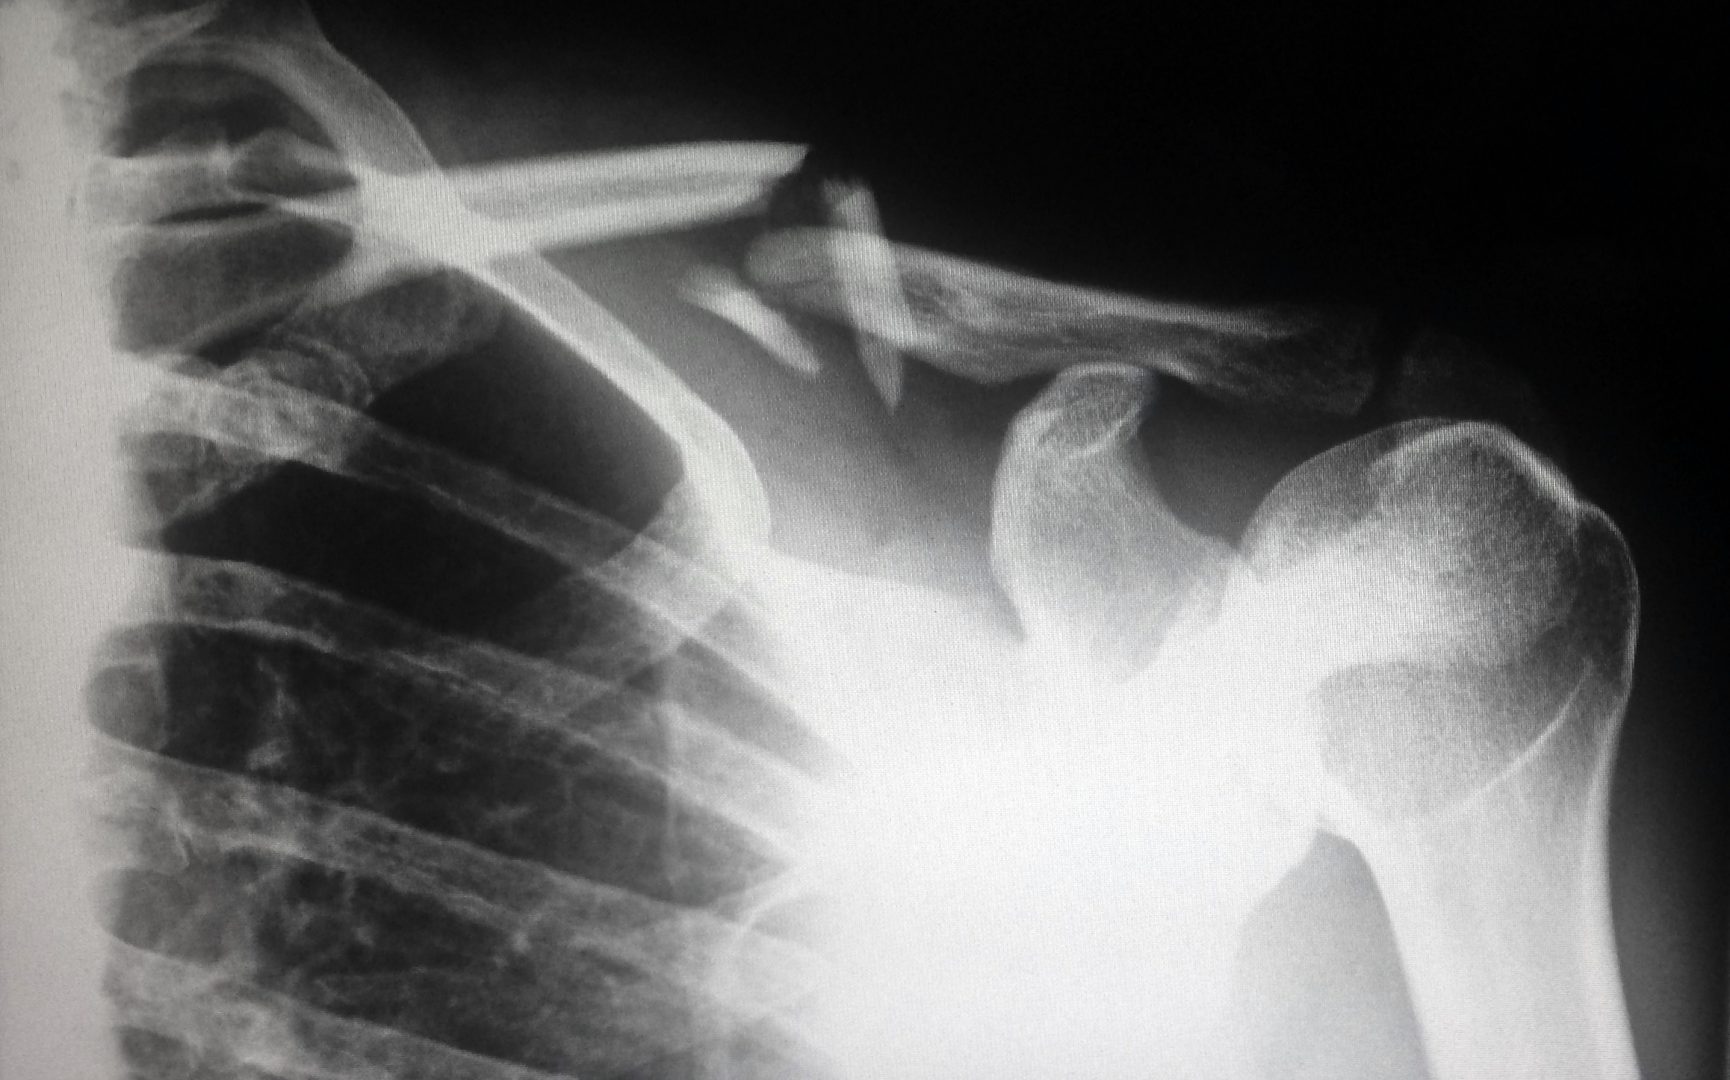

Siitä tietää olevansa nelikymppinen, kun krempat hiipivät keskusteluihin. Nelikymppisiltä kuulee usein: ”Vanhuus ei tule yksin”, yleensä vielä tässä vaiheessa leveän hymyn kera. Kaikenlaista pientä vaivaa putkahtelee siellä täällä ja paino nousee, vaikka mitä tekisi. Enää ei voi syödä mitä tahansa, koska vatsa kuplii ja kipuilee. Verenpaine, kolesteroli ja hiusraja ovat koholla. Niveliä kolottaa (etenkin kun on matalapaine), ja vähintään joka toisella on nivelrikkoa – aika usein liiallisesta tai vääränlaisesta treenaamisesta. Moni nelikymppinen sallii jo itselleen lepoa ja rauhaa; crossfitit ja ultramaratonit on niin nähty, ja kaikkien kokeilujen seurauksena on löytynyt se oma laji. Nelikymppinen kehtaa jo tunnustaa, että tavallinen kävely metsässä riittää vallan hyvin nostamaan sykettä – ja ennen kaikkea toimii hyvin niin kovin tärkeäksi muodostuneeseen mielen tasaamiseen.

Siitä tietää olevansa nelikymppinen, kun krempat hiipivät keskusteluihin. Nelikymppisiltä kuulee usein: ”Vanhuus ei tule yksin”, yleensä vielä tässä vaiheessa leveän hymyn kera. Kaikenlaista pientä vaivaa putkahtelee siellä täällä ja paino nousee, vaikka mitä tekisi. Enää ei voi syödä mitä tahansa, koska vatsa kuplii ja kipuilee. Verenpaine, kolesteroli ja hiusraja ovat koholla. Niveliä kolottaa (etenkin kun on matalapaine), ja vähintään joka toisella on nivelrikkoa – aika usein liiallisesta tai vääränlaisesta treenaamisesta. Moni nelikymppinen sallii jo itselleen lepoa ja rauhaa; crossfitit ja ultramaratonit on niin nähty, ja kaikkien kokeilujen seurauksena on löytynyt se oma laji. Nelikymppinen kehtaa jo tunnustaa, että tavallinen kävely metsässä riittää vallan hyvin nostamaan sykettä – ja ennen kaikkea toimii hyvin niin kovin tärkeäksi muodostuneeseen mielen tasaamiseen.